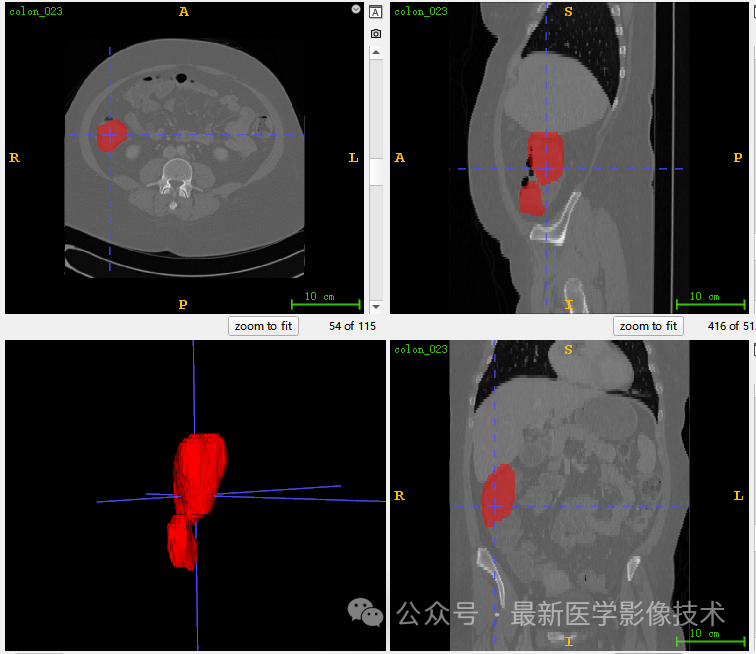

6、测试集分割结果